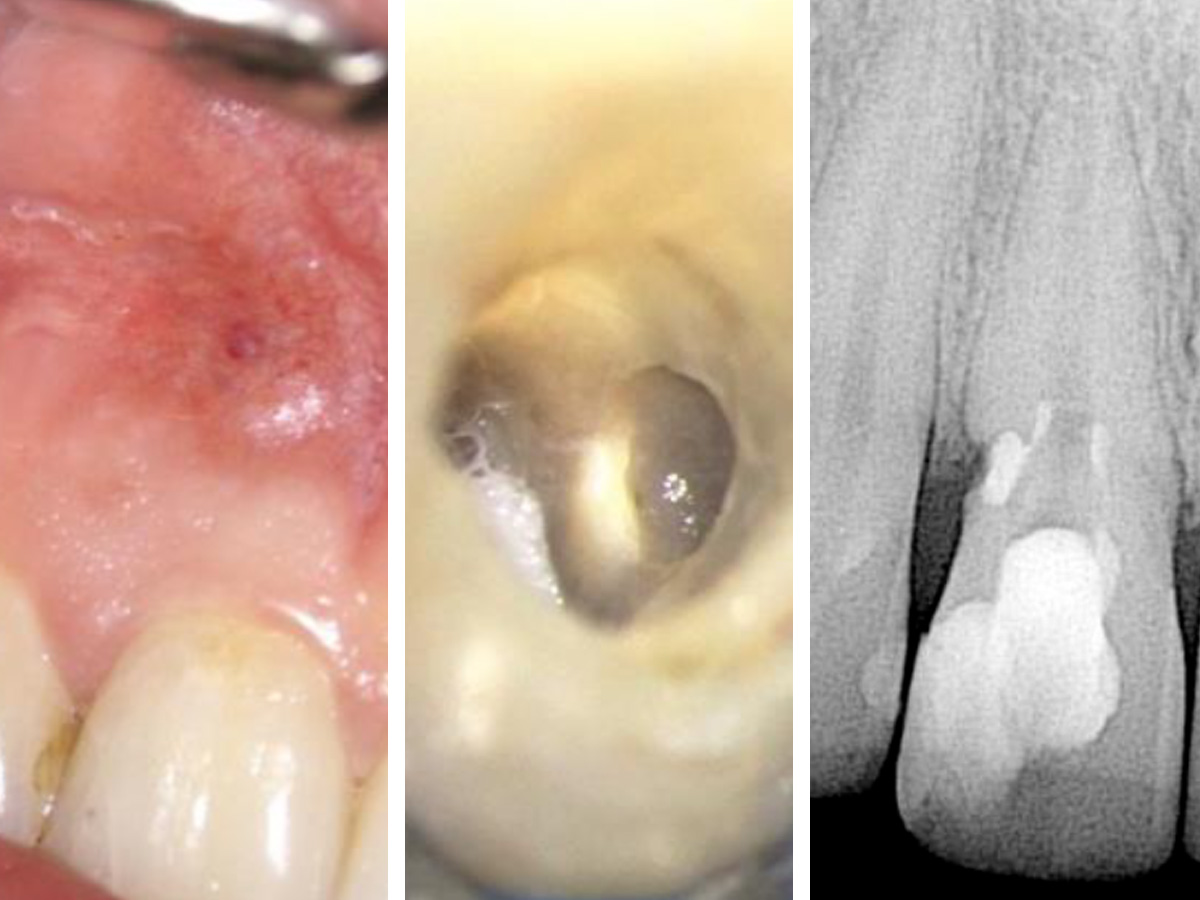

Abbildung 1

Klinische und röntgenografische Ansichten zeigen eine Fistelbildung, die bei genauerer Untersuchung zu einem distal liegenden, zervikalen Defekt an Zahn 11 führte.

Abbildung 2

Zu sehen ist der blutende Defekt im zervikalen Bereich zu Beginn der Wiedereröffnung des Wurzelkanals.

Der geöffnete Zugang zeigt die Gutta-Percha im koronalen Kanal und das BC Putty im resorptiven Defekt. Das Röntgenbild zeigt die Situation direkt nach der Behandlung.